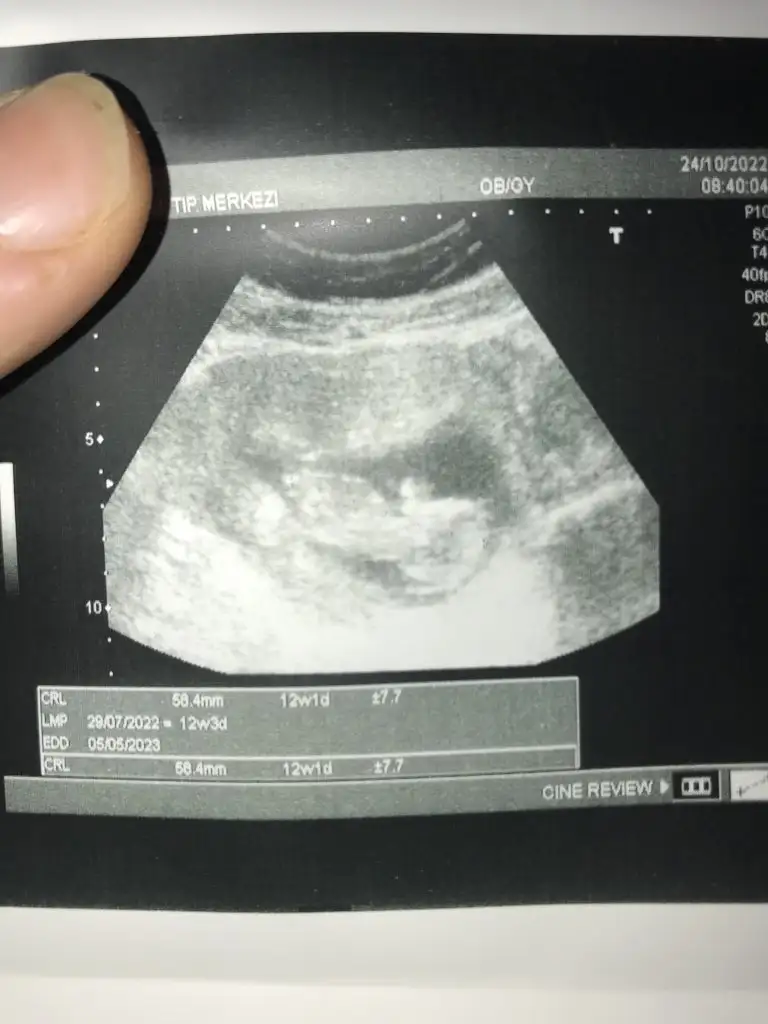

5 ve 14. haftaya kadar olan ultrason fotolarınızı paylaşın. Vajinadan mı yoksa karından mı çekildiğini ve kaç haftalık olduğunu da mutlaka belirtin.